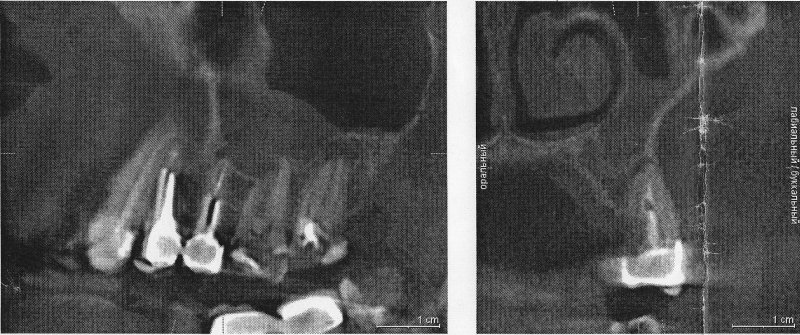

При рентгеновском обследовании в стоматологической клинике случайно обнаружили грубые подушковидные утолщения слизистой в базальных и вентральных отделах левой верхнечелюстной полости. При этом у зуба 2.4 расширена периапикальная щель, разрежение костной ткани у верхушки корня, у зуба 2.5 у верхушки корня небольшая гранулёма, над ней разрушена компактная пластина дна верхнечелюстной полости, у верхушек корней зуба 2.7 гранулёмы, компактная пластина дна верхнечелюстной полости над гранулёмами местами не прослеживается.

Зубы 2.4 и 2.5 удалили, 2.7 собираются лечить, но перед лечением посоветовали обратиться к ЛОРу. Не понимаю, почему не наоборот.